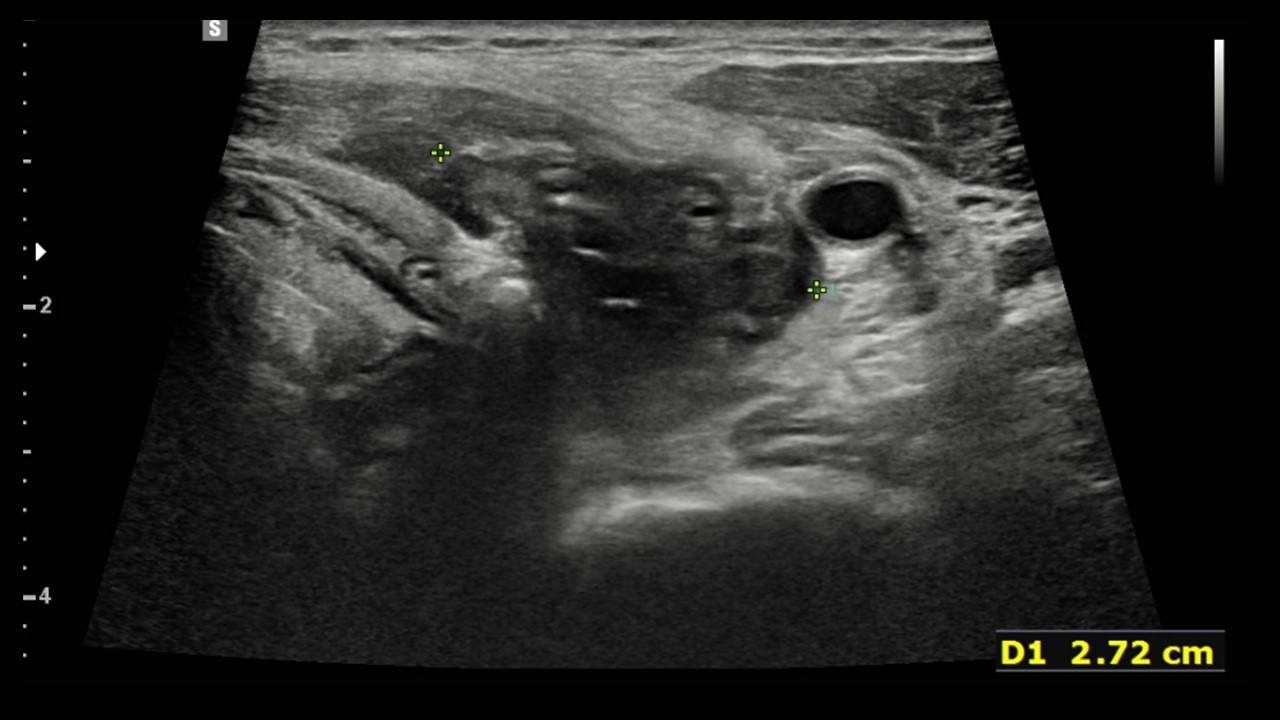

[369,] 48/F,Sore throat, neck pain

Modality

US,CT,

What is the most likely diagnosis?

[Diagnosis]

1.

Hypopharynx cancer with thyroid invasion

2.

Infected 4th branchial cleft anomaly

3.

Infected thyroglossal duct cyst

4.

Anaplastic thyroid cancer

5.

Infected 3rd branchial cleft anomaly